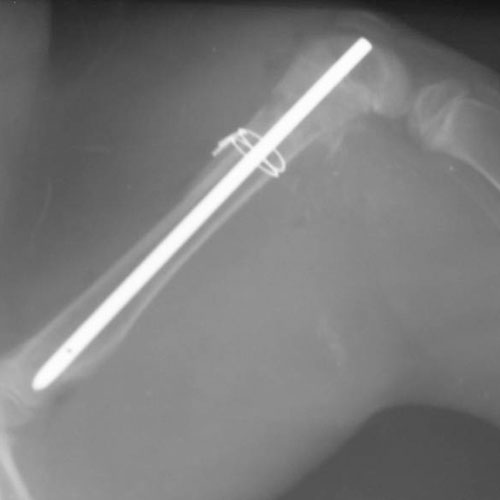

Как рассказал заведующий хирургическим отделением Евгений Козлов, рентгенограммы показали, что дела обстоят не столь радужно — у маленького сервала перелом бедренной кости.

— Требовалась довольно сложная операция металлоостеосинтеза, — поясняет доктор. — Хирургическая бригада принялась за работу, не откладывая дела в долгий ящик. Мы провели предоперационное обследование экзотического котенка, а ассистенты обработали операционное поле. Анестезиологи рассчитали дозу анестетиков, погрузили усатого пациента в наркоз, и за дело взялись хирурги.

Сервалу провели репозицию и стабилизацию костных отломков при помощи интрамедуллярного стержня. Затем малыша отправили обратно в родной вольер под зоркое наблюдение ветеринарных специалистов зоологического парка. А на днях состоялось повторное обследование хирурга.

— Котенок уже находится в открытом вольере, опороспособность и функция конечности восстановлена на сто процентов, — говорит Евгений Козлов. — Быстро отросшая шерсть полностью скрыла следы травмы и нашего вмешательства. Маленький сервал окреп и шустро бегает по своей территории. Сторонний посетитель ни за что не догадается, что какая-то из четырех пятнистых лап прячет в себе «железную штуковину».